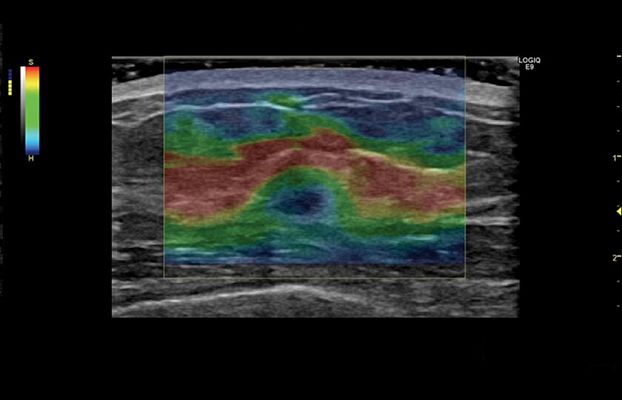

Клинические изображения

- Strain Elastography - программа эластографии.

- Elastography Q-analysis + CF/PDI Quantification - программа количественного анализа для эластографии и анализа васкуляризации в режиме ЦДК и ЭД.

- Эластография сдвиговой волны и компрессионная эластография — технологии неинвазивной оценки упругости тканей.